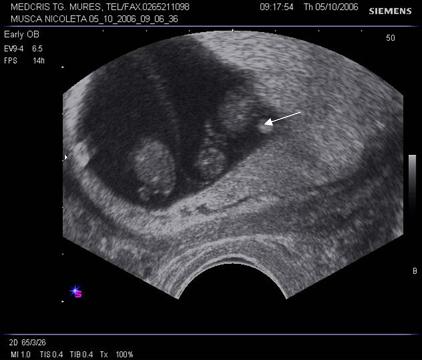

Fig nr 6 Decolare de pol inferior ( cu sageata ) la o sarcina de 7 sapt

Fig. nr. 66. Aceeasi sarcina, ca in figura precedenta, la 12 saptamani , fara imagini patologice la polul inferior ovular, marcat cu sageata

Fig nr. 67 Decolare de pol inferior ovular, situat in continuarea canalului cervical

( sageata) la ecografia transvaginala